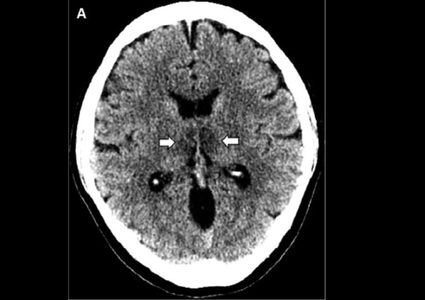

Woman diagnosed With COVID-19 develops rare brain disease

A woman believed to be the first person to suffer from a rare type of brain swelling following a diagnosis of COVID-19 which might be ...